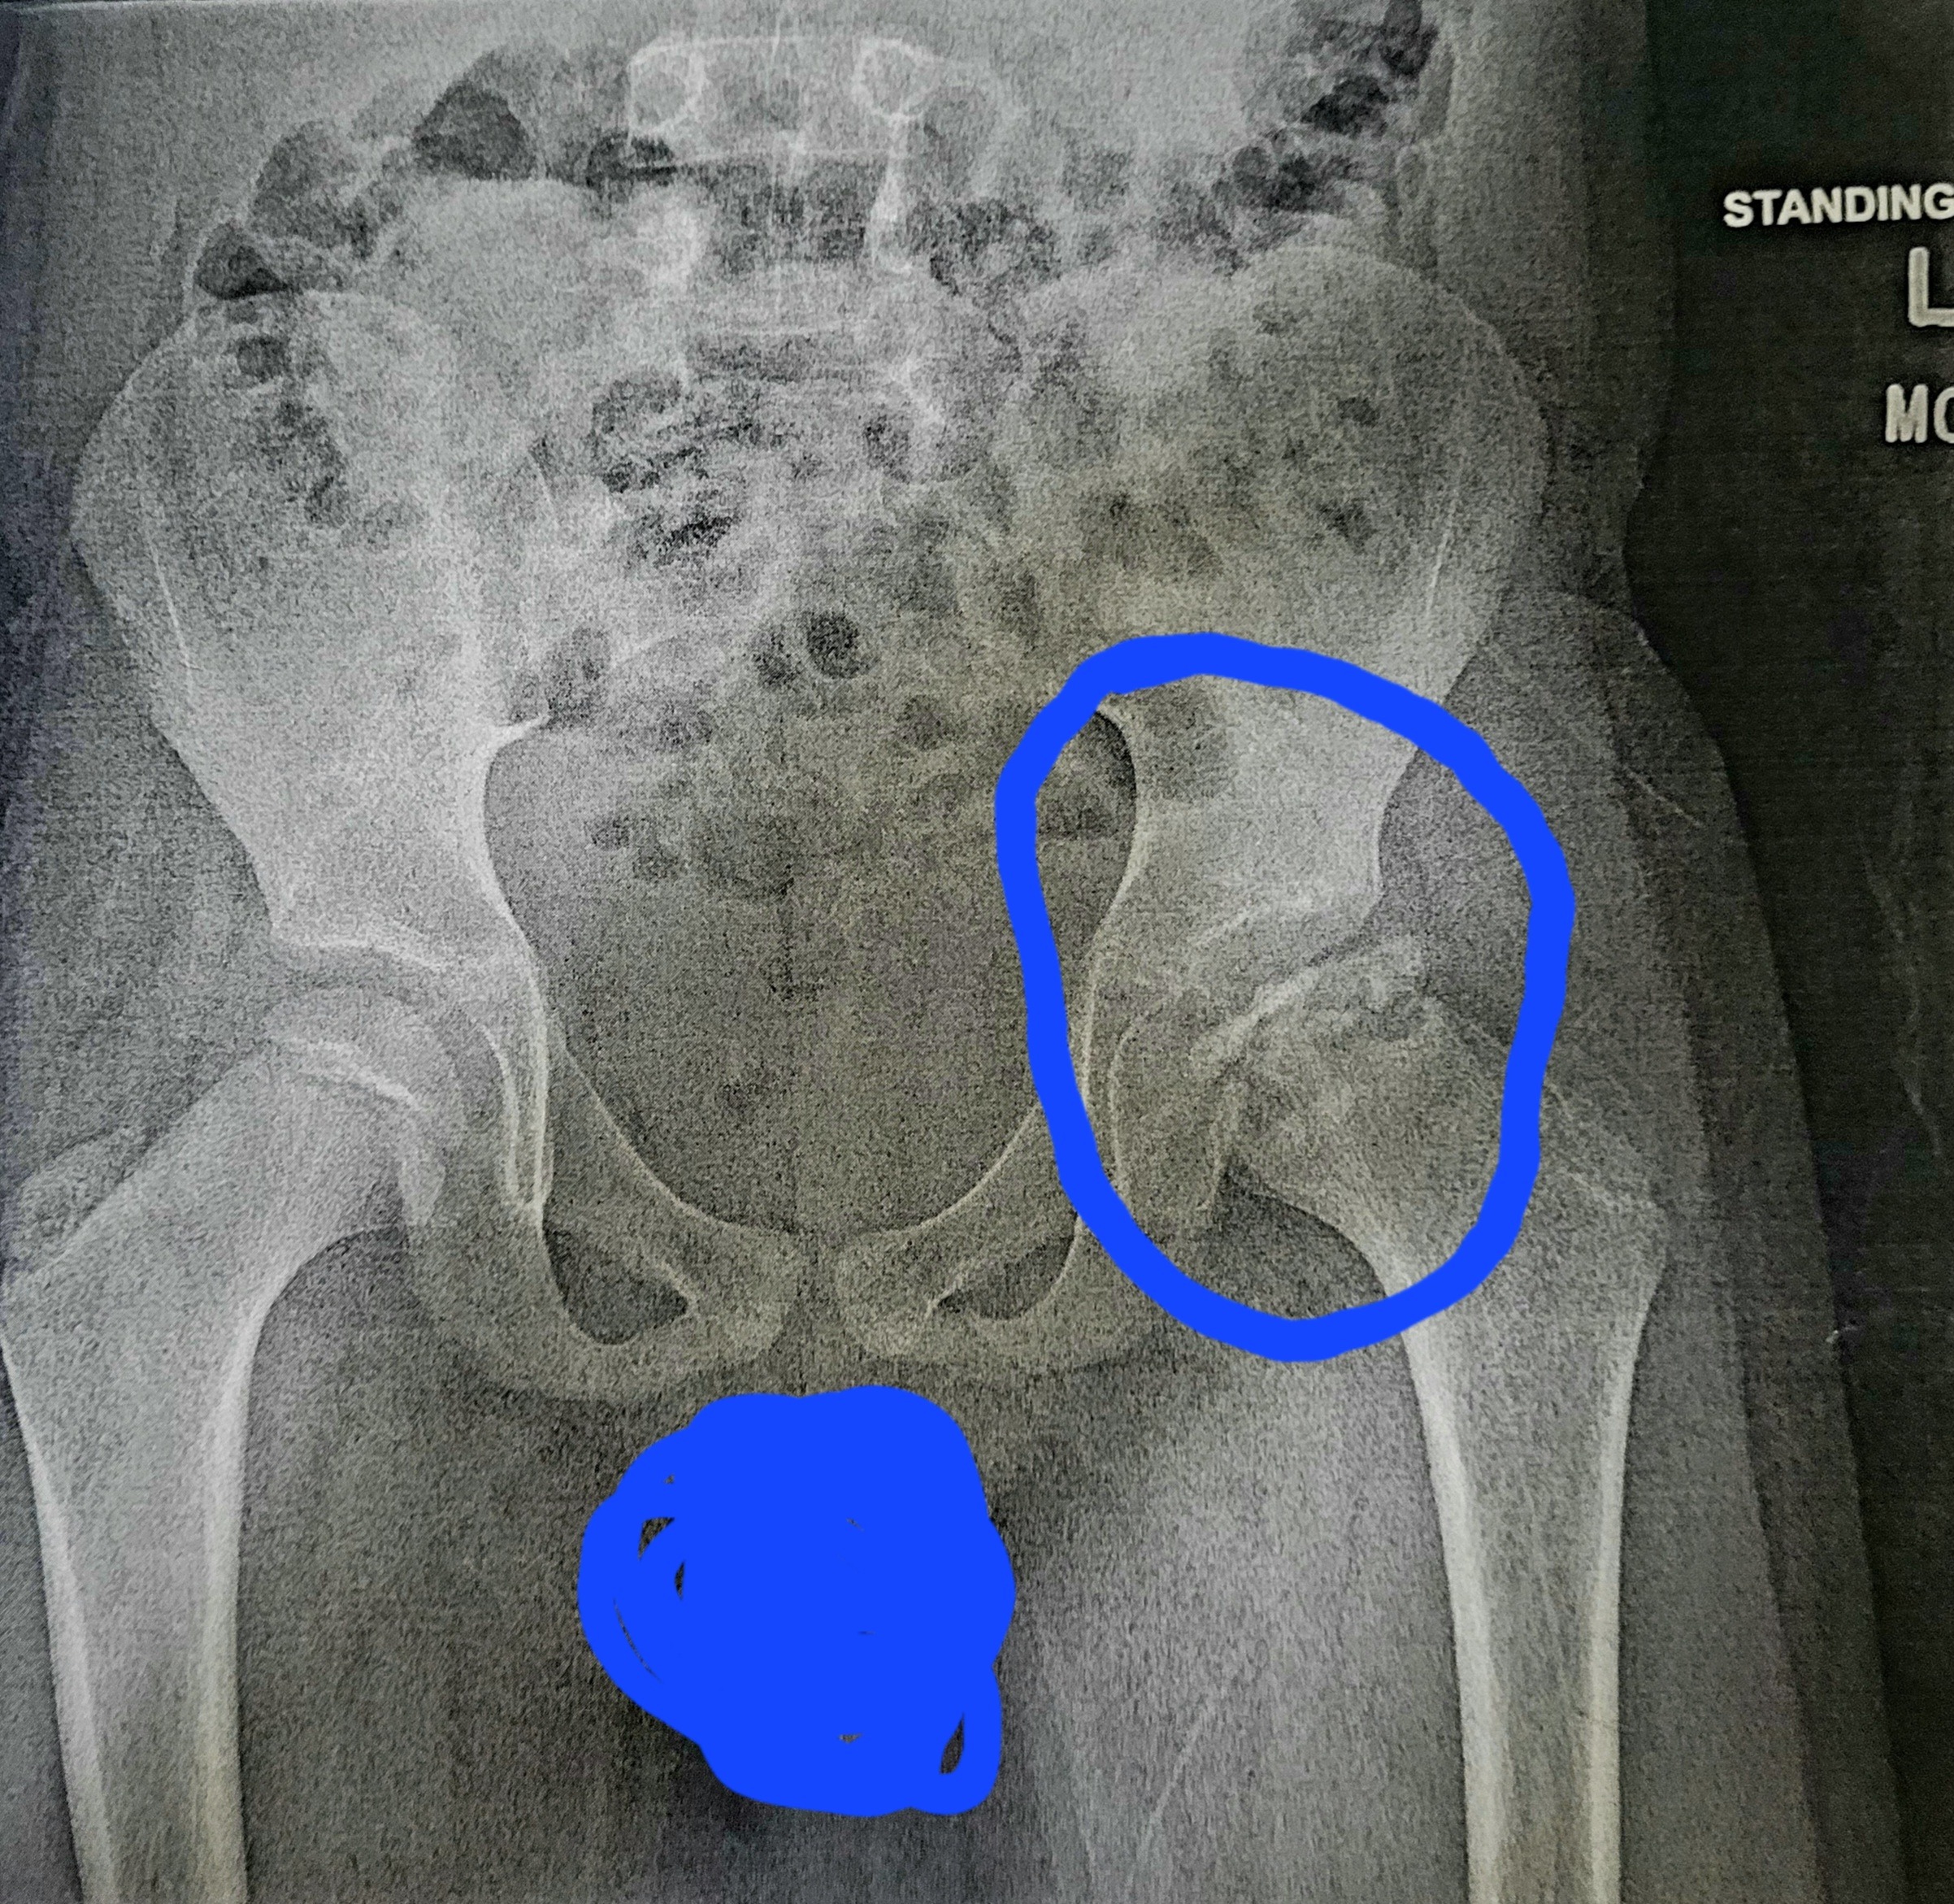

Our son Nash, who is 8 years old, was diagnosed with a rare bone condition in his left hip called Legg-Calvé-Perthes disease in September 2024 after a 2-week period of an unexplained limp. This rare bone disease has caused the head of his femur to die (necrosis) due to a loss of blood supply (avascular). The exact cause of this condition remains unknown, and there is no known cure. The main goal is to keep the head of his femur inside of his hip socket.

Nash and his dad flew to Texas to see a doctor who specializes in Perthes disease on August 26th. This doctor has put Nash in a wheelchair and walker and has made him totally non-weight bearing on his left leg. We will fly back to Texas on September 23rd to get a Petrie cast (a cast that will hold his legs as far apart as they can go) put on for 6 weeks. After the cast is removed, he will regain strength in his leg for a couple of weeks, then fly back to Texas and get a Triple Pelvic Osteotomy. They will cut Nash's pelvic bone in 3 spots and move it down to fit over the head of his femur better.